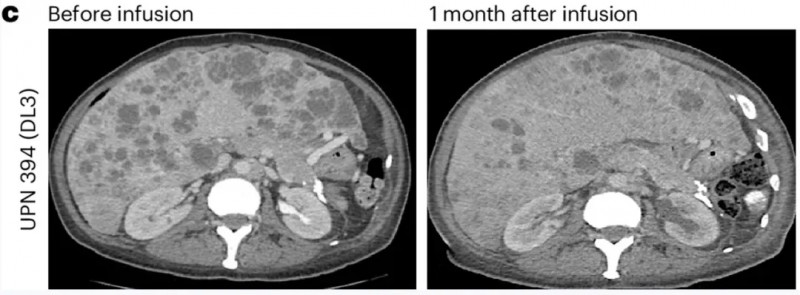

第一例为DL3剂量组患者(UPN394),其肝转移负荷实现放射学改善,但未达到PSA反应;CT扫描清晰呈现了输注前的肝转移灶,以及输注PSCA-CAR-T细胞1个月后的疾病反应(详见下图c)。

▲图源“Nature Medicine”,版权归原作者所有,如无意中侵犯了知识产权,请联系我们删除